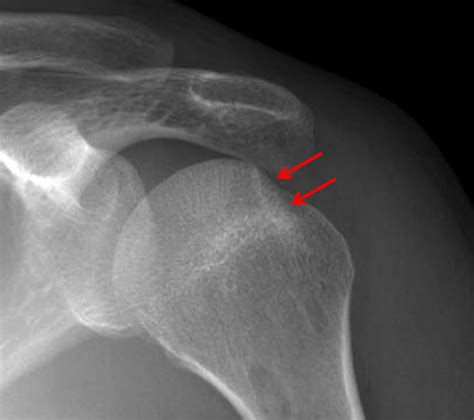

• X-rays: These can help identify fractures and dislocations but may not always show the Hill Sachs lesion clearly.

• CT Scan (Computed Tomography): This can offer a more detailed view of the bone structure and is often used to assess the extent of the fracture.

A Hill Sachs Fracture is a specific type of injury that occurs in the shoulder joint. It involves a compression fracture of the humeral head, which is the upper part of the arm bone that fits into the shoulder socket. This fracture typically results from a dislocation of the shoulder, where the humeral head is forced out of its socket and then impacts the glenoid rim, causing a depression or fracture on the humeral head.